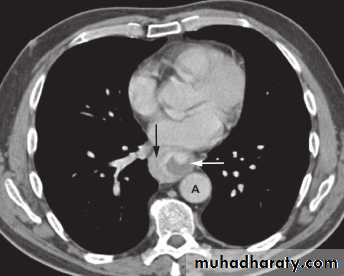

Stricture

Benign vs. malignant Causes Specific locationContrast study EUS CT